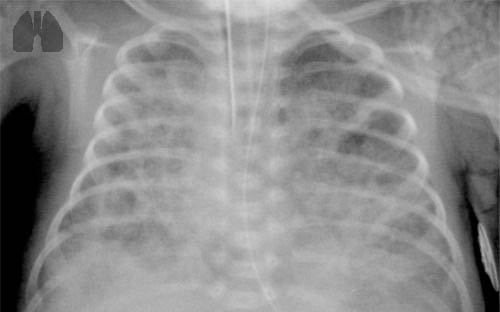

FIGURE 1

Infants with bronchopulmonary dysplasia (BPD) are typically born pre-term, and often require mechanical ventilation.